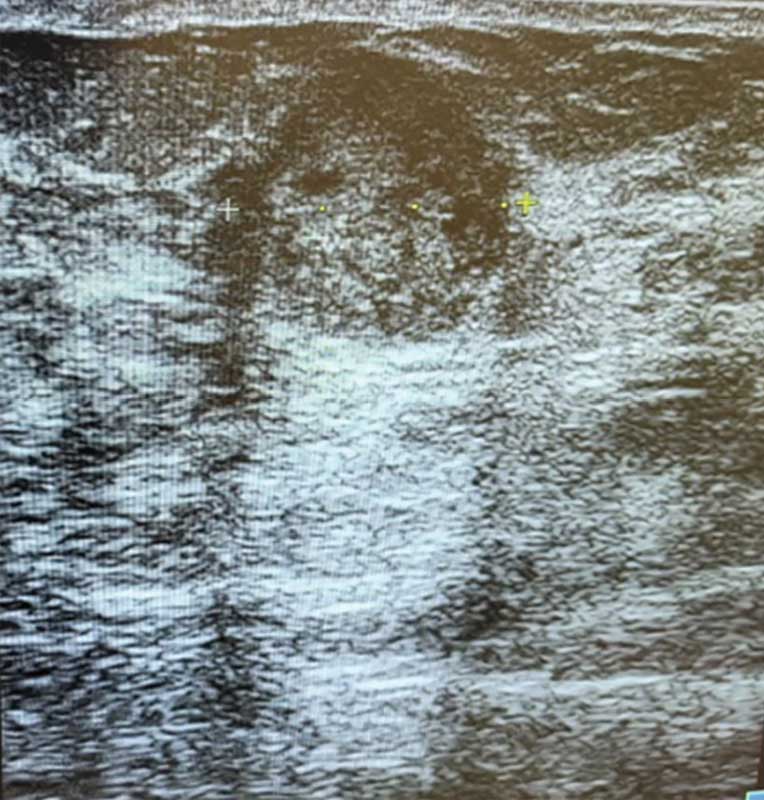

Рис. 3. Ювенильная фиброаденома правой молочной железы у 15-летней девочки

Опухоли подразделяют на доброкачественные и злокачественные [1, 5]. У девочек наиболее распространена ювенильная фиброаденома – доброкачественная фиброэпителиальная опухоль, обычно возникающая в пубертате и склонная к быстрому росту (рис. 2) [5, 11, 12]. Чаще это одиночный узел. Множественные очаги отмечают примерно у каждой пятой пациентки, двусторонние – примерно у каждой десятой [5, 12, 13].

На УЗ-картине солидное, гипоэхогенное по сравнению с тканью МЖ образование однородной структуры, с четкими контурами. Нередко наблюдается дорсальное псевдоусиление без акустической тени (рис. 3–5) [5, 7, 10].